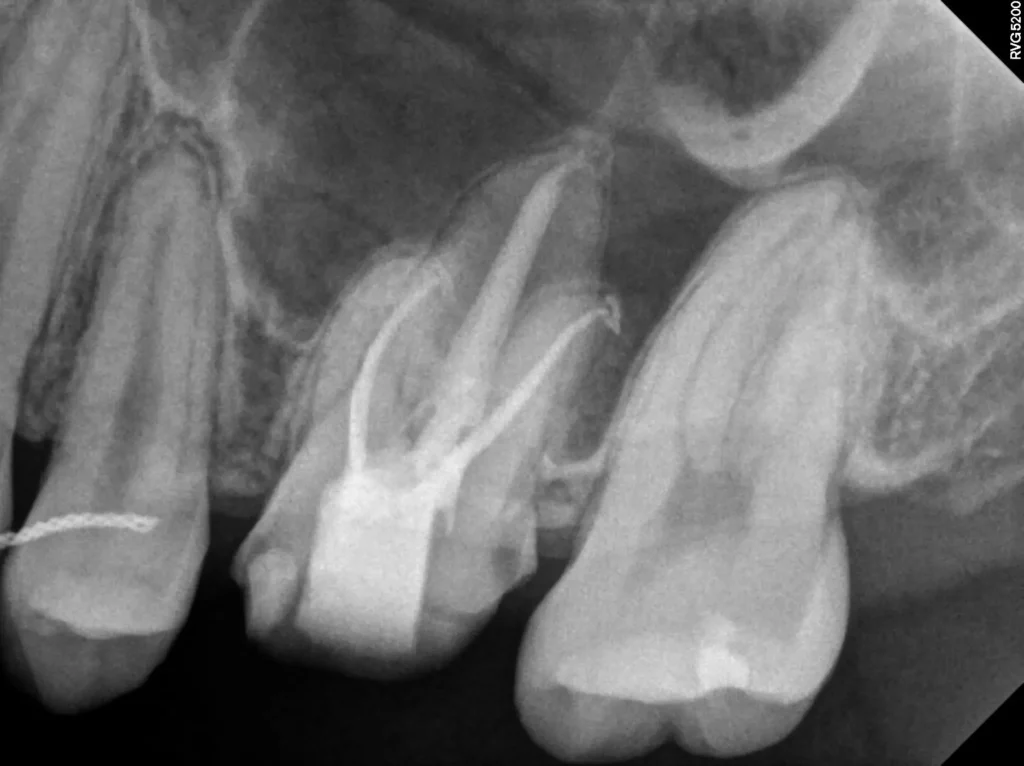

육안으로 볼 때는 치아가 깨끗해 보였습니다. 하지만 X-ray 촬영 결과는 달랐습니다. 기존에 치료된 레진 하방으로 깊은 충치가 관찰되었습니다. 신경관과 거의 닿아 있을 정도로 아주 깊은 상태였습니다. 충치가 깊어 신경과 가까울수록 레진 치료 시 접착에 매우 신경 써야 합니다. 접착이 완벽하지 않으면 치아와 레진 사이 경계면이 계속 자극을 받습니다.

시간이 지나면 신경이 예민해집니다. 결국 신경치료가 필요한 상태로 악화됩니다. 환자분은 치료 직후부터 6개월 이상 시림 증상을 겪으셨습니다. 진단 결과 해당 치아(#26번)는 비가역적 치수염(Pulpitis) 상태였습니다. 이미 신경이 회복 불가능한 상태라 신경치료를 결정했습니다.

STEP 1 (1회차) 신경치료를 시작합니다. 모든 신경관을 찾아 정리하고 깨끗이 소독합니다.

STEP 2 (2회차) 신경치료를 마무리(근관충전)합니다. 치아를 다듬고 본을 뜹니다.

STEP 3 (3회차) 일주일 뒤 제작된 최종 보철물(지르코니아)을 세팅합니다. 모든 치료가 종료됩니다.